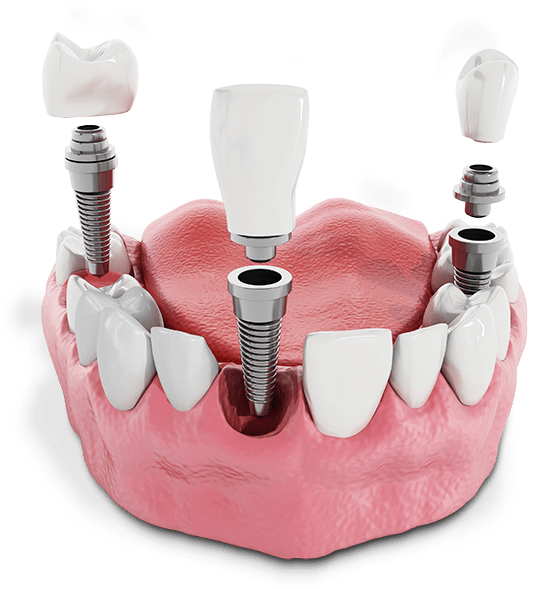

When teeth go missing, the bone structure that once held them in place is no longer needed and the body will allow it to shrink. This process, called resorption, can lead to many problems, one of which is that insufficient bone volume makes it impossible to rebuild your smile with dental implants. In some cases, bone grafting procedures can rebuild the bone volume. However, bone grafting is not an ideal option for every case. In some cases, the anatomy of your upper jaw cannot accommodate the normal placement of dental implants.

Traditionally, dental implants are placed in the crest of bone that once supported the teeth. This approach may be impossible for many patients for a variety of reasons including the shape and position of their sinuses or a history of bone loss. Zygomatic implants use the cheekbones (zygomatic arches) as a strong, stable foundation for specialized dental implant posts toward the front of your upper arch. Pterygoid implants similarly use alternative bone structures of the skull as anchor points closer to the back of the mouth.

There are many benefits to zygomatic and pterygoid implants. They require fewer surgeries or alterations such as bone grafting. They offer reliable, long-term functions for a secure bridge of teeth that will look and feel completely natural. In many cases, we can even immediately place crowns so you can start living life to the fullest without waiting for your final restorations!

Although zygomatic and pterygoid implants might sound more invasive than conventional treatments, they can be placed in one surgical procedure without additional bone grafting. We may also place conventional dental implants strategically to reinforce your final bridge for ideal longevity and function. Because no bone grafting is necessary for this treatment, we can often complete your treatment process faster and provide you with a functional, beautiful new smile more quickly than conventional treatment.

We’ll place immediate temporary restorations so you can live your life to the fullest while your implants heal over the next several months. Once your implants fully integrate with the bone tissue, you’ll return for your final restorations, custom-crafted from strong, resilient ceramic for ideal esthetics and function. With pterygoid and zygomatic dental implants from Blooming Dental & Implant Center, you’ll love your smile for life!